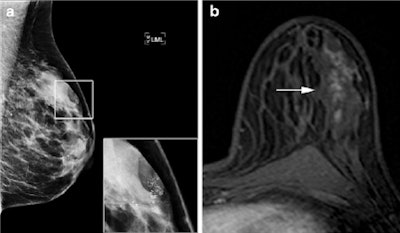

At pathology, 40 of 123 (33%) lesions proved malignant, and 70% of those were DCIS, the rest were invasive carcinoma. The two observers detected all invasive malignancies at MRI, as well as 79% (observer 1) and 86% (observer 2) of in situ lesions. MRI in addition to conventional imaging led to a significant increase in area under the receiver operating characteristic (ROC) curve from 0.67 to 0.79 for observer 1 and to 0.80 for observer 2.

However, only low- and intermediate-grade DCIS are affected in this instance and not high-grade DCIS or invasive carcinomas -- in fact, almost all the DCIS lesions detected on MRI were high-grade in the study.

"In the end, DCIS is regarded as a potential precursor lesion of invasive disease, and is therefore treated with breast-conserving therapy followed by radiation therapy," they wrote. "Our results do show an added diagnostic value of 3T breast MRI to conventional imaging, but unfortunately MRI does not exclude DCIS lesions of all grades sufficiently in all cases, and its sensitivity is not high enough to replace biopsy."